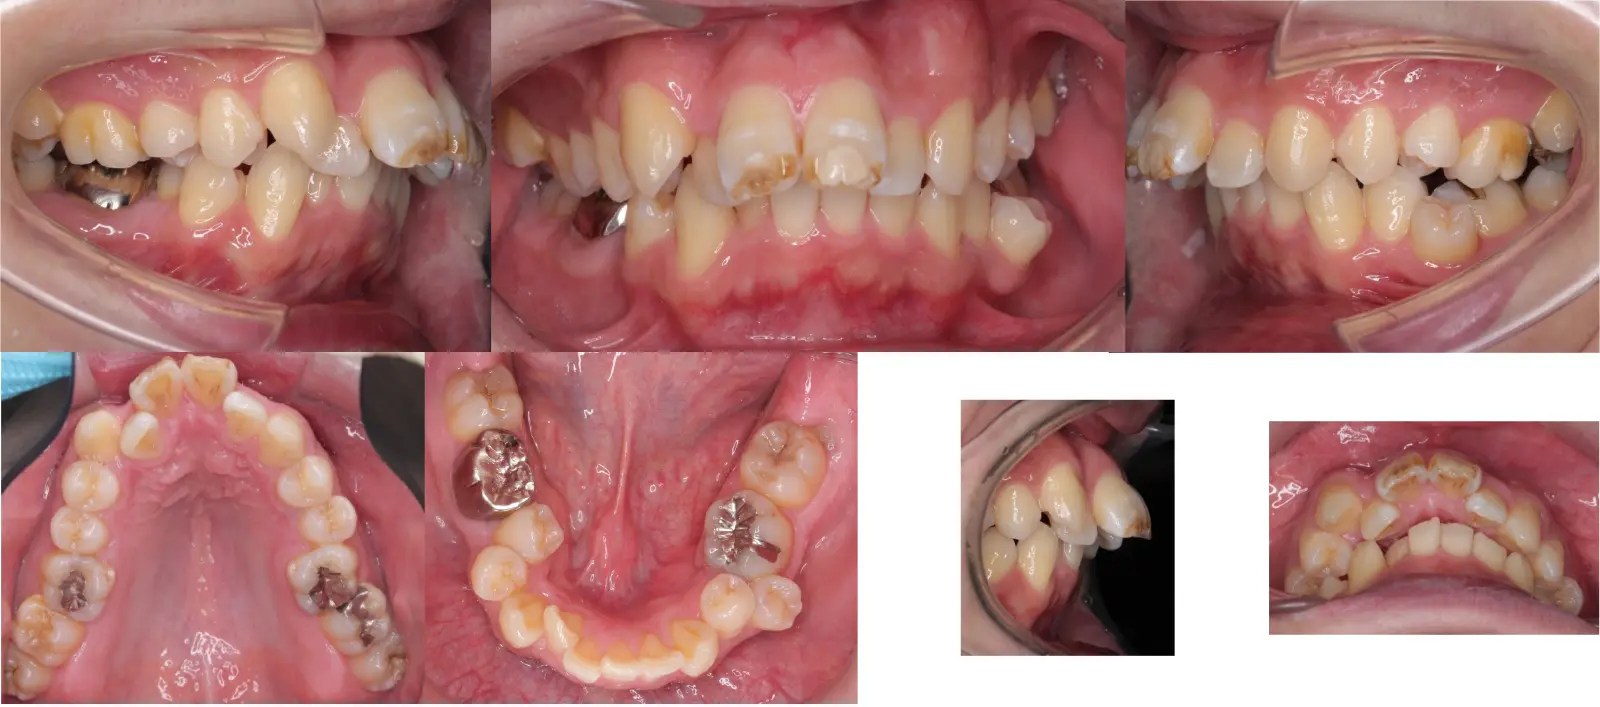

アングル1級叢生と過蓋咬合を伴う上顎前突症

- 主訴

口元の突出感と乱食歯

- 年齢

10代

- 治療期間

1年5ヶ月

- 治療回数

16回

- 治療に用いた主な装置

カスタムメイド型マルチブラケットタイプのデジタル矯正装置(インシグニア)

- 治療費

630,000円(税別)、調整料5,000円(税別)

- 抜歯部位

上下顎第一小臼歯 計4本